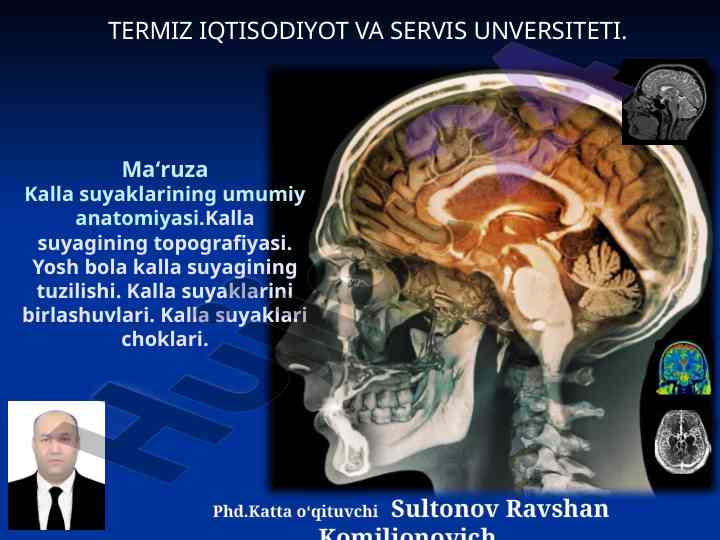

Kalla skeleti tanishuv va umumiy ma'lumotlar

Kalla skeleti va chakka suyagi haqida umumiy ma'lumotlar taqdim etilgan o‘quv qo‘llanma. Anatomiyaga oid asosiy tushunchalar va strukturalar izohlangan.